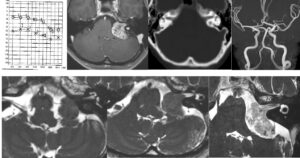

視力障害、記銘力障害で発症した頭蓋咽頭腫を両側前頭開頭、anterior interhemispheric approachで切除しました。トルコ鞍部や鞍上部にはほとんど局在しないためtranslamina-terminalis approachを選択しました。視床下部動脈を温存し、内減圧を繰り返し、焼き鳥テクニックとリングキュレットで狭い術野から腫瘍を起こして摘出しました。術後年齢が比較的若かったためかすぐに覚醒しました。